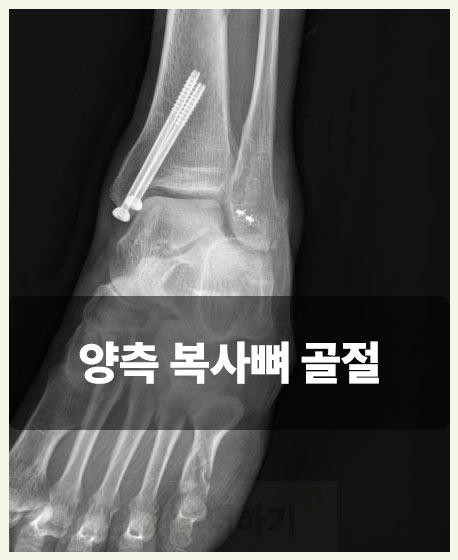

복사뼈는 발목의 복숭아뼈를 말하는데요. 주로 넘어지거나 발을 잘못 디뎌 부상이 생깁니다. 바깥쪽과 안쪽 복숭아뼈를 각각 외과(외복사), 내과(내복사)라고 하며 이중 한곳만 다치기도 하지만 심한 경우 두 곳이 모두 골절되기도 합니다.

실제 보상 사례 양쪽 복사뼈 골절 s82820

■ 사건 요약 사례자분은 출근길에 일어난 사고로 양측 복사뼈 모두 골절되는 부상을 입어 금속 핀으로 고정하는 수술을 하셨습니다. 다행히 출퇴근 재해로 산재 처리하여 치료비, 휴업급여, 장해급여가 지급되었습니다. 이후에는 개인보험 청구도 했는데요. 실비를 청구하여 비급여 치료비 일부와 골절 진단비, 수술비 등도 받으셨습니다. ■ 후유장해 기준 검토 이 외 가장 중요한 것이 바로 장애에 대한 보상이죠. 오 ** 님은 양쪽 복숭아뼈를 모두 다쳐 발목 운동 범위가 상당히 제한된 상태였습니다. 이에 해당되는 약관의 장애 기준을 다음 표로 간단히 살펴볼 수 있습니다.